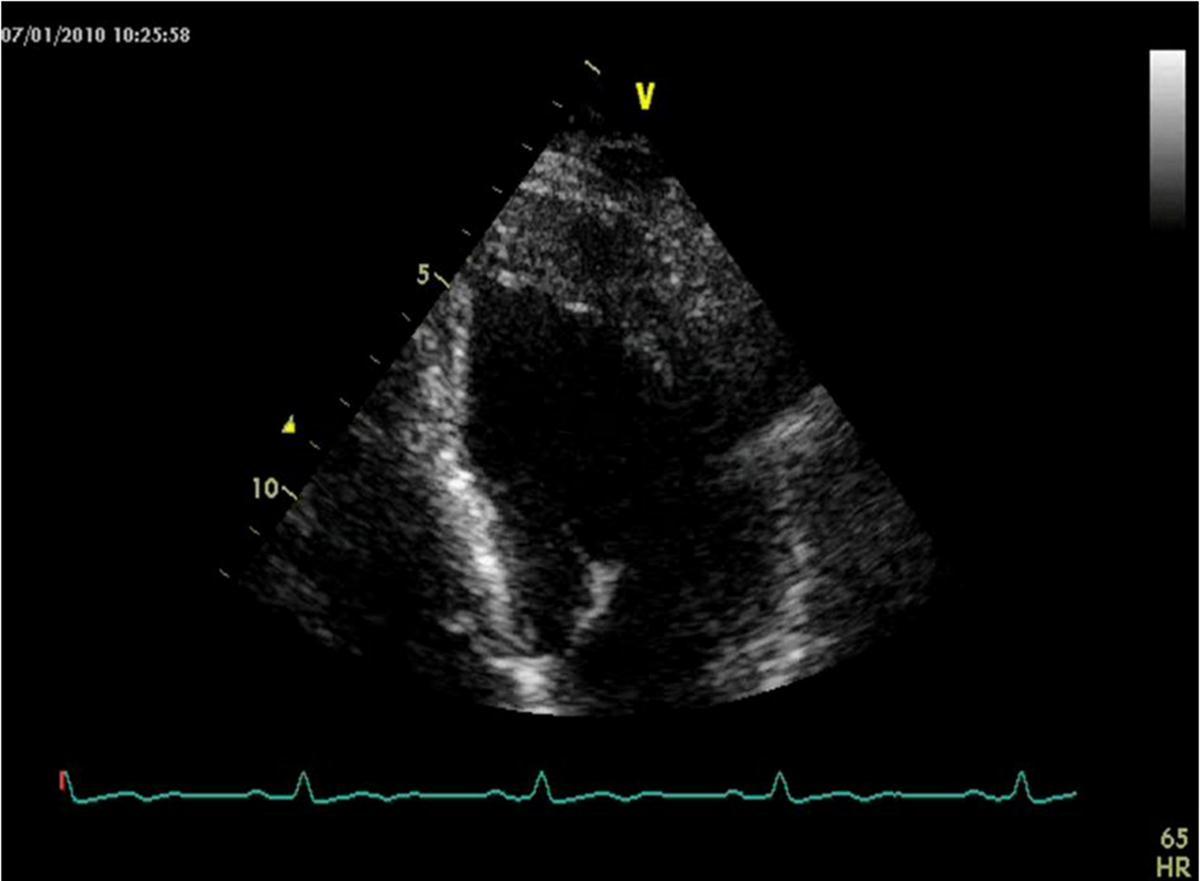

He was asymptomatic, in good general conditions, blood pressure 120/80 mmHg, no murmurs. The electrocardiogram showed sinus bradycardia (55 bpm) and left ventricular hypertrophy signs (deep and symmetric negative T waves in DI, aVL, V2 till V6). Echocardiogram (VIVID 7, 2-4 MHz probe) showed non classical apical hypertrophic cardiomyopathy (Figure 2), localized at anterior, lateral and posterior apex (septum was preserved), with no obliteration of apical cavity. By mean of color-Doppler evaluation, we observed multiple and thin color flows from LAD draining into apical region. Pulse-wave Doppler temporization was exclusively diastolic (Figure 3). Stress echocardiography with accelerate dipyridamole resulted negative for inducible ischemia and no variation in fistula flow was detectable. Inguinal hernia intervention was safely performed and the patient was advised to undergo periodical cardiologic controls.

Figure 2.Echocardiogram image of non classical apical hypertrophic cardiomyopathy of the patient.